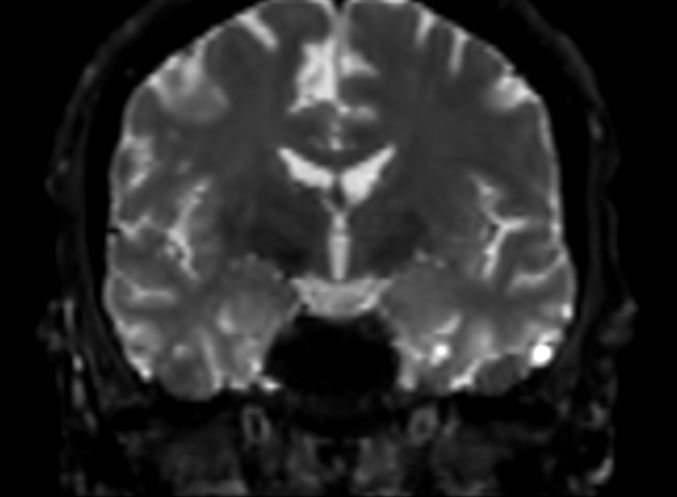

DWI b1000 (coronal reformat)